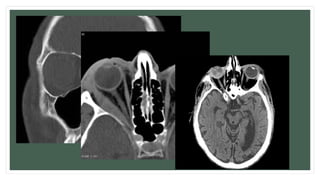

• C.T: (coronal cut) teardrop sign, polypoid mass consists of herniated orbital contents, periorbital

fat and inferior rectus muscle. The affected sinus is partially opacified on radiograph. Air-fluid

level in maxillary sinus due to presence of blood.

Diagnosis: Imaging: • Water’s viewshows a convex opacity bulging into the antrum from the above. • C.T: (coronal cut) teardrop sign, polypoid mass consists of herniated orbital contents, periorbital fat and inferior rectus muscle. The affected sinus is partially opacified on radiograph. Air-fluid level in maxillary sinus due to presence of blood. • MRI: Detection of Inflammatory myopathy, Optic nerve condition, Vitreous haemorrhage.